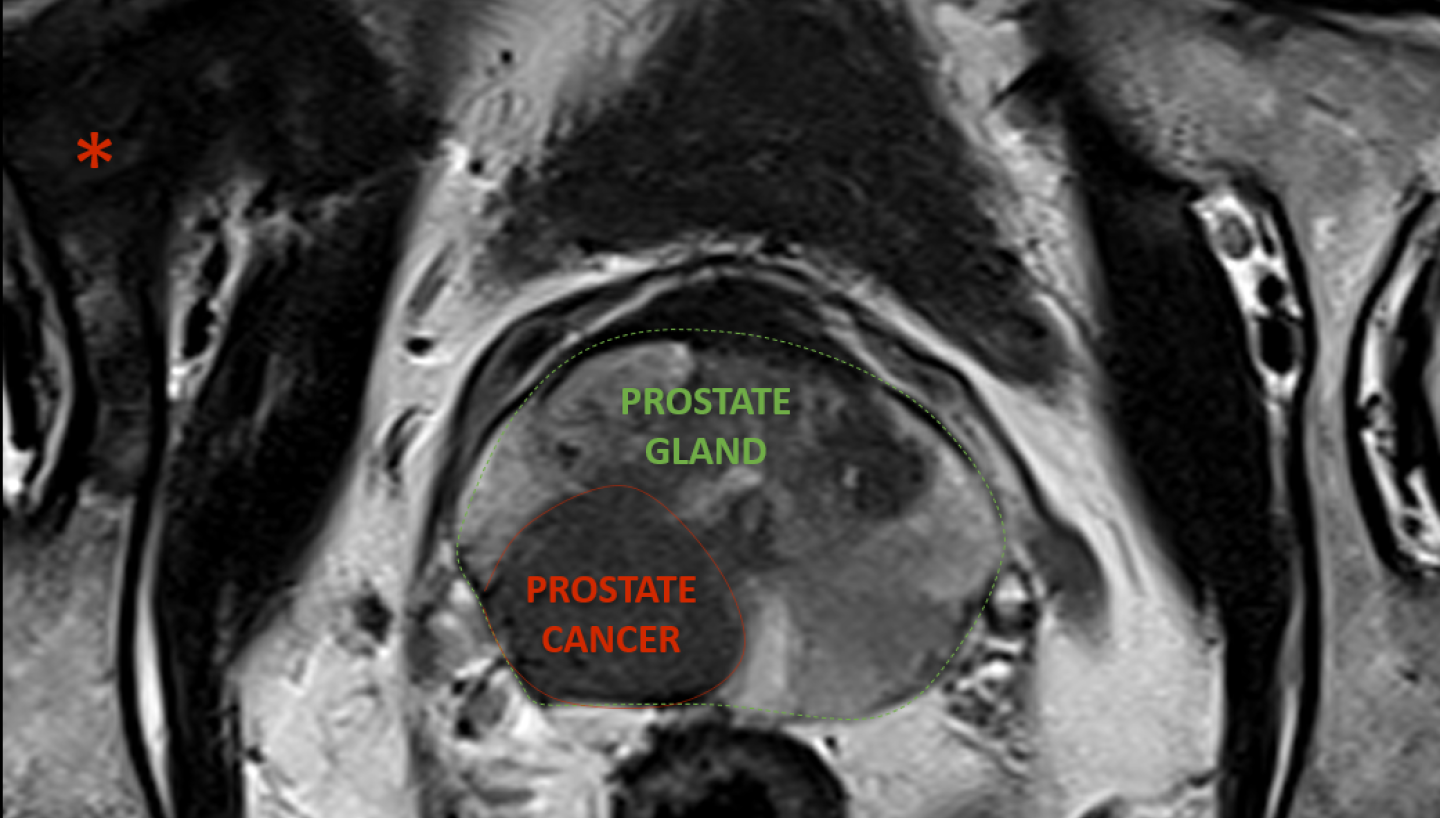

The pelvic floor is a complex area, so if the cause of symptoms isn’t clear, or if surgery is being considered, additional imaging may be helpful to understand how the pelvic floor is functioning. This involves dynamic imaging (where you’re asked to bear down or have a bowel motion) using special X-rays, ultrasound, or a MRI scan.  At Canopy Imaging, we use MRI to assess pelvic floor problems, and have trained staff who specialise in this type of imaging.

Pelvic floor MRI (Magnetic Resonance Defaecating Proctography) is a specialised scan that uses magnetic fields to create images of your pelvic organs and muscles, allowing our team to see how these structures move when you're relaxing, straining, and passing a bowel motion. The scan is non-invasive, painless, and does not use radiation.

Pelvic floor MRI allows doctors to assess both the pelvic organs and the support structures (muscles and ligaments), and to identify problems such as prolapse, blocked bowel emptying (obstructed defaecation), internal folding of the bowel (intussusception), or problems coordinating the pelvic floor muscles (dyssynergia).